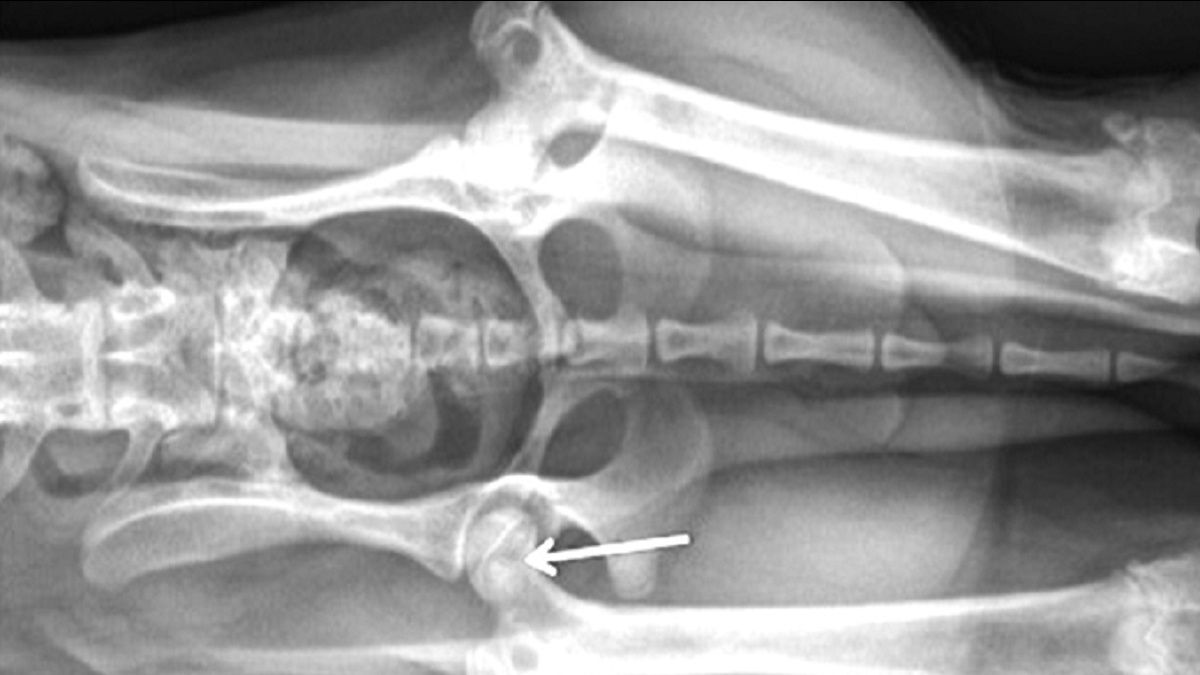

Exérèse tête et col du fémur. La flèche noire indique la région de l’acétabulum crânial (la zone blanche située sous la flèche est le cartilage articulaire de l’acétabulum. Le tissu à l’extrémité de la flèche est le reste de ligament de la tête fémorale). L’accolade montre le fémur après ostéotomie et exérèse tête et col. L’ostéotomie va de la face médiale du grand trochanter jusqu’au petit trochanter.

Figure 3. Exérèse tête et col du fémur. La flèche noire indique la région de l’acétabulum crânial (la zone blanche située sous la flèche est le cartilage articulaire de l’acétabulum. Le tissu à l’extrémité de la flèche est le reste de ligament de la tête fémorale). L’accolade montre le fémur après ostéotomie et exérèse tête et col. L’ostéotomie va de la face médiale du grand trochanter jusqu’au petit trochanter.© Darryl L. Millis

Suture de la capsule articulaire dorsale de l’acétabulum (flèche blanche) avec la capsule ventrale (flèche noire). La capsule formera une couche de tissus mous entre l’acétabulum et le fémur ostéotomisé, indiqué par l’accolade.

Figure 4. Suture de la capsule articulaire dorsale de l’acétabulum (flèche blanche) avec la capsule ventrale (flèche noire). La capsule formera une couche de tissus mous entre l’acétabulum et le fémur ostéotomisé, indiqué par l’accolade.© Darryl L. Millis

Pour obtenir d’excellents résultats avec l’ETCF, il est essentiel d’adopter une bonne technique opératoire. Un abord crâniolatéral de l’articulation coxofémorale est réalisé et la capsule articulaire est exposée. Une arthrotomie est effectuée en incisant la capsule articulaire juste au-dessus de son insertion sur le col du fémur. Le ligament rond est sectionné et la tête fémorale est luxée vers l’extérieur. Un instrument de type crochet à ovariectomie peut être utilisé pour surélever la tête fémorale par rapport à l’acétabulum et aider à protéger le nerf sciatique qui longe caudalement le col fémoral. Une petite scie électrique, une scie fil ou un ostéotome et un marteau peuvent être utilisés pour réaliser l’ostéotomie. Dans certains cas, l’os peut être très mou ou fracturé et une pince-gouge peut alors suffire à retirer le reste de la tête fémorale. Pour tenir compte de l’antéversion de la tête et du col, il faut appliquer une rotation externe suffisante au fémur, en amenant par exemple la pointe du tarse (tuber calcis) contre la paroi thoracique latérale. L’ostéotomie est effectuée de la base du grand trochanter jusqu’au petit trochanter (Figure 3). Après ETCF, il est nécessaire de palper le site d’ostéotomie pour détecter tout éclat d’os restant, généralement sur la face caudomédiale du fémur. Le cas échéant, les excroissances osseuses peuvent être retirées avec une pince gouge et le site d’ostéotomie peut ensuite être lissé à l’aide d’une râpe. Puis, la zone est abondamment rincée pour éliminer les fragments restants ou les poussières d’os. La néoarticulation est mobilisée pour s’assurer qu’il n’existe pas de contact interosseux important. La partie de la capsule articulaire venant du bord dorsal de l’acétabulum peut alors être suturée sur la face ventrale de l’acétabulum pour interposer une couche de tissu mou entre l’acétabulum et le fémur ostéotomisé (Figure 4). Des radiographies postopératoires doivent être réalisées pour confirmer que la totalité de la tête et du col a bien été retirée (Figure 5).